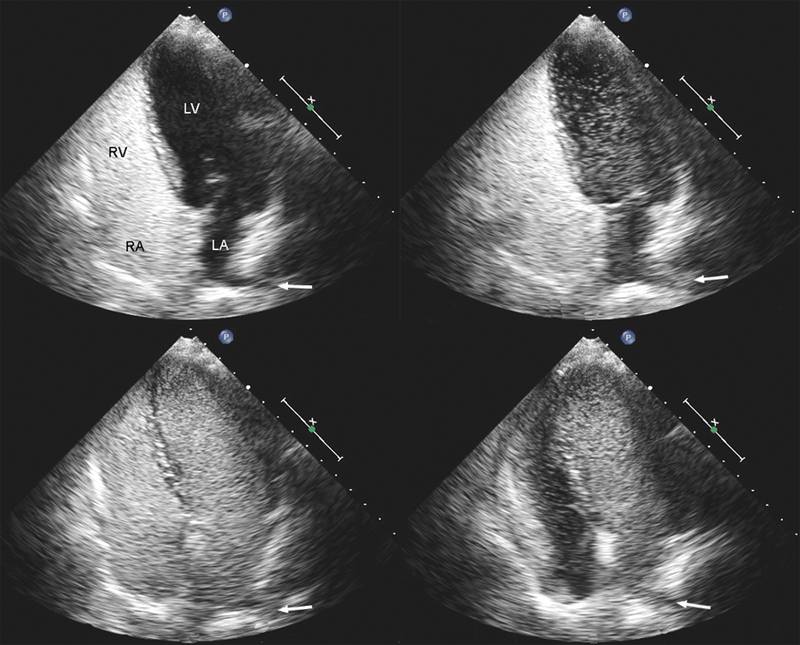

فحوصات تشخيصية لبعض امراض القلب والشرايين التاجية